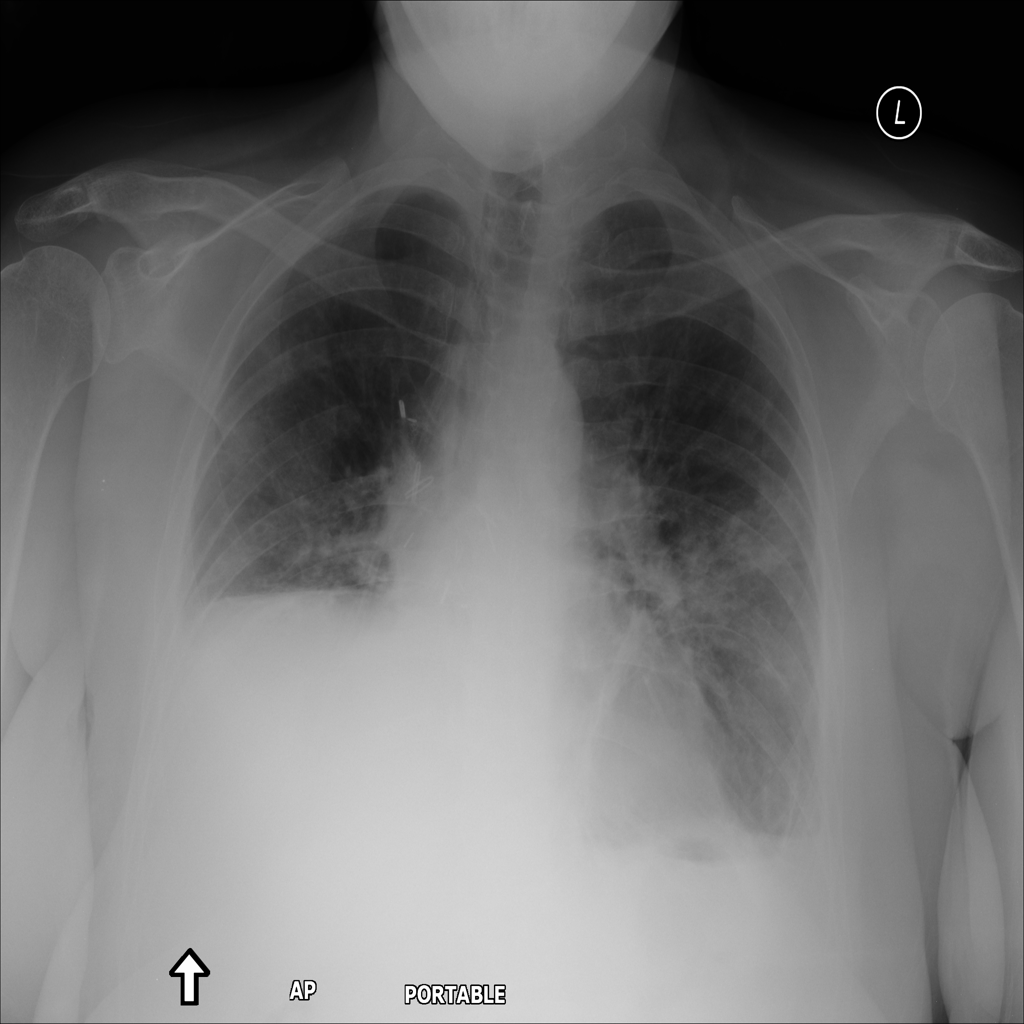

PAT-4639 · IMG-021Effusion

PAT-4639 · IMG-021

PA